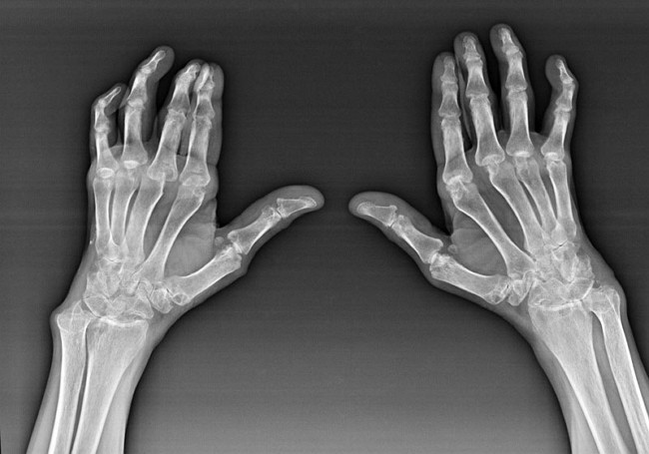

Revmatoidni artritis

Revmatoidni artritis je bolezen, pri kateri človeški imunski sistem poškoduje telesna lastna tkiva. Z drugimi besedami, revmatoidni artritis je avtoimunska patologija. Ta bolezen je tudi sistemska, saj nanjo vpliva veliko tkiv (mišice, sklepi, posode itd.) in organe (Srce, ledvice, pljuča itd.) v telesu.

Kljub temu, da je revmatoidni artritis sistemska bolezen pod njim, v večji meri trpijo sklepi, medtem ko je lezija drugih tkiv in organov v ozadju. S to boleznijo lahko prizadene skoraj vse vrste krtačih sklepov (zapestne stene, karpalne poti, metacarpal-falanx, medfalanks). Lezija je običajno simetrična (te. So prizadeti isti spoji) na obeh rokah, ki jih spremlja oteklina, bolečina v poškodovanih sklepih. Zjutraj je med dvigom iz postelje nekaj togosti v prizadetih sklepih, ki lahko trajajo približno 1 uro in nato izginejo brez sledu.

Precej pogosto z revmatičnim artritisom v bližini prizadetih sklepov krtače (pogosteje klavir-falanks, medfalanksni sklepi) Pojavijo se revmatoidne vozliče. So zaobljena tvorba, ki se nahaja pod kožo. Na krtači te formacije najpogosteje nastanejo na hrbtni strani. Ob palpaciji so goste, neaktivne, neboleče. Število jih lahko razlikuje.